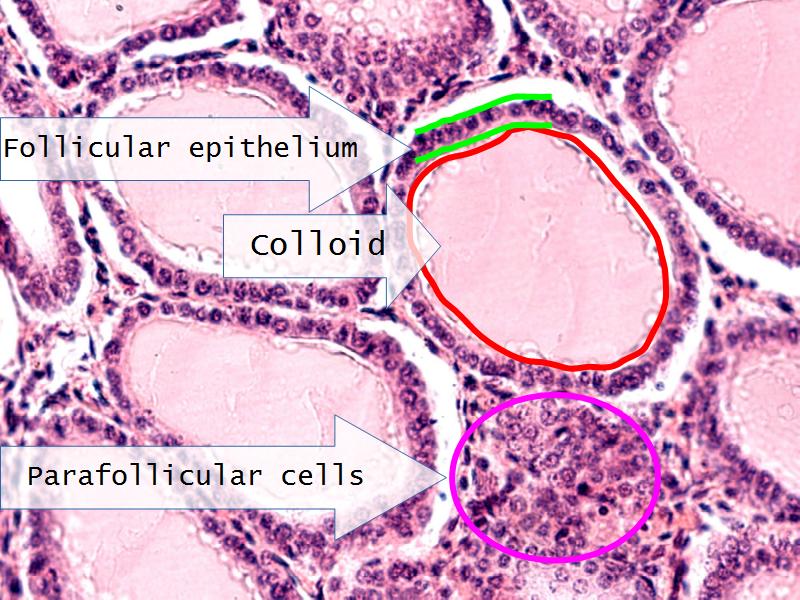

Thyroid gland

Four elements making up the thyroid

Thyroid gland

- Follicle

- Follicular epithelium

- Parafollicular cells

- Colloid

- Identify them on the next slide